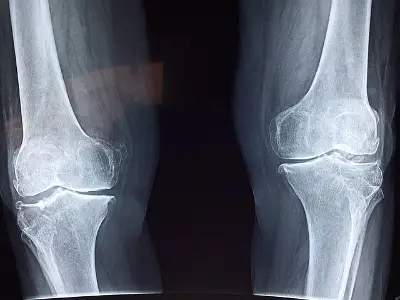

노화가 진행됨에 따라 점점 더 많은 사람들이 뼈 건강에 대한 우려를 느끼게 됩니다. 이는 특히 뼈가 약해짐에 따라 작은 충격에도 골절이 자주 발생할 수 있기 때문입니다.

이 글에서는 골밀도 검사와 관련된 자세한 정보 및 비용에 대해 설명하고, 뼈 건강을 유지하기 위한 예방 조치에 대해서도 심도 있게 살펴보겠습니다. 또한, 뼈 건강의 중요성을 강조하며, 나이가 들어감에 따라 더욱 많은 사람들이 이러한 문제에 직면하게 되는 이유를 알아보겠습니다.

뼈 건강은 단순히 신체적인 면에 그치지 않고, 전반적인 삶의 질에도 깊은 영향을 미칩니다. 나이가 들수록 뼈가 약해지는 현상은 자연스러운 과정이지만, 이를 방치하면 큰 문제가 될 수 있습니다.

골밀도 검사(BMD)는 골다공증을 진단하는 데 필수적이며, 주로 DEXA 방법을 사용하여 진행됩니다. 검사 결과는 T-score와 Z-score를 통해 제공되며, 이를 통해 자신의 뼈 상태를 정확히 파악할 수 있습니다.

골밀도 검사는 단순한 검사 이상으로, 개인의 뼈 건강 상태를 지속적으로 모니터링하고 적절한 조치를 취할 수 있도록 도와줍니다. 골밀도 검사를 통해 얻는 정보는 장기적인 건강 관리에 중요한 역할을 하며, 뼈 건강을 유지하기 위한 기초적인 자료로 활용됩니다.